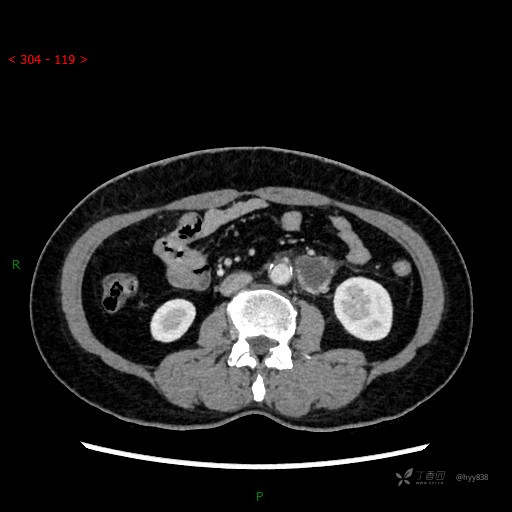

静脉期

CT平扫是外院的,因图像质量原因,不方便上传!